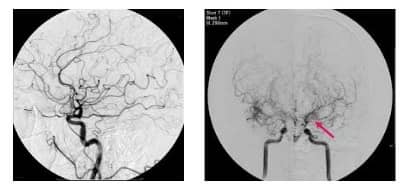

모야모야병은 뇌의 주요 혈관들이 점차 좁아지는 질병입니다. 이로 인해, 뇌에 필요한 혈액 공급이 제대로 이루어지지 않게 됩니다. 이런 현상을 보완하기 위해 뇌 내의 작은 혈관들이 활성화되어 더 많이 형성됩니다.

이 작은 혈관들의 형태가 연기처럼 흐르는 모양을 닮아 '모야모야'라는 이름이 붙여진 것입니다. 이 이름은 일본어에서 유래하였으며 연기가 구름처럼 피어오르는 모양을 뜻하는 말에서 비롯되었습니다.

모야모야병은 뇌혈관조영술로 진단되며, 자세한 뇌혈류 검사 결과에 따라 치료가 진행됩니다.